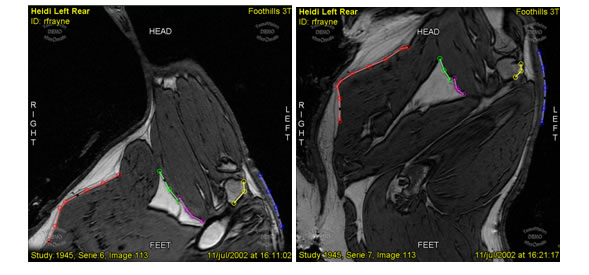

- Automatic registration of medical imagery (Figure 6).

Figure 6: Registration of medical images